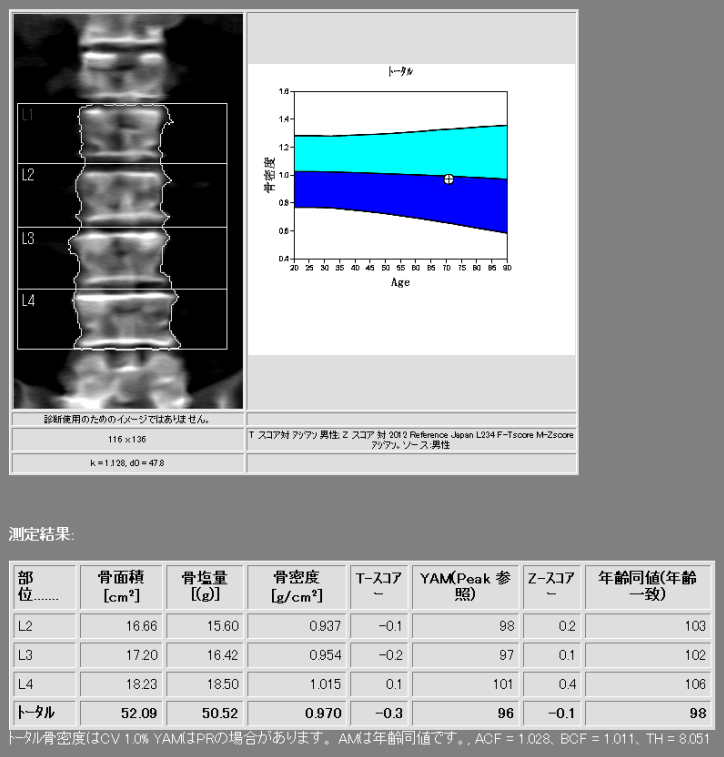

骨密度検査

骨密度検査とは、骨の中にあるカルシウムなどのミネラル量を測定し、骨粗鬆症や骨折のリスクを診断するための検査です。検査では、骨折リスクの高い部位とされる腰椎や大腿骨頚部を主に測定し、概ね5~10分程度の短時間で行うことができます。また、検査データを蓄積できるので、定期的に検査を行うことで前回との比較や年齢に応じた変化や、骨粗鬆症の早期発見と予防、治療効果の確認に役立てる事ができます。

当院では、HOLOGIC社製Horizon Wiを使用し、2種類の異なるエネルギーX線を使用するDXA法(二重エネルギーX線吸収測定法:Dual-energy X-ray Absorptiometry)による高精度な測定を行い、骨強度の指標であるTBS(骨質評価:Trabecular Bone Score)も算出可能となっています。